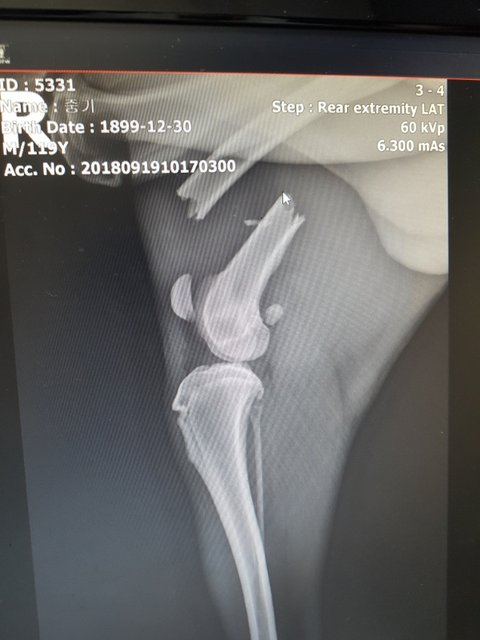

역시나 다발성 골절..

골반뼈와 오른쪽 뒷다리가 부러져 있었습니다